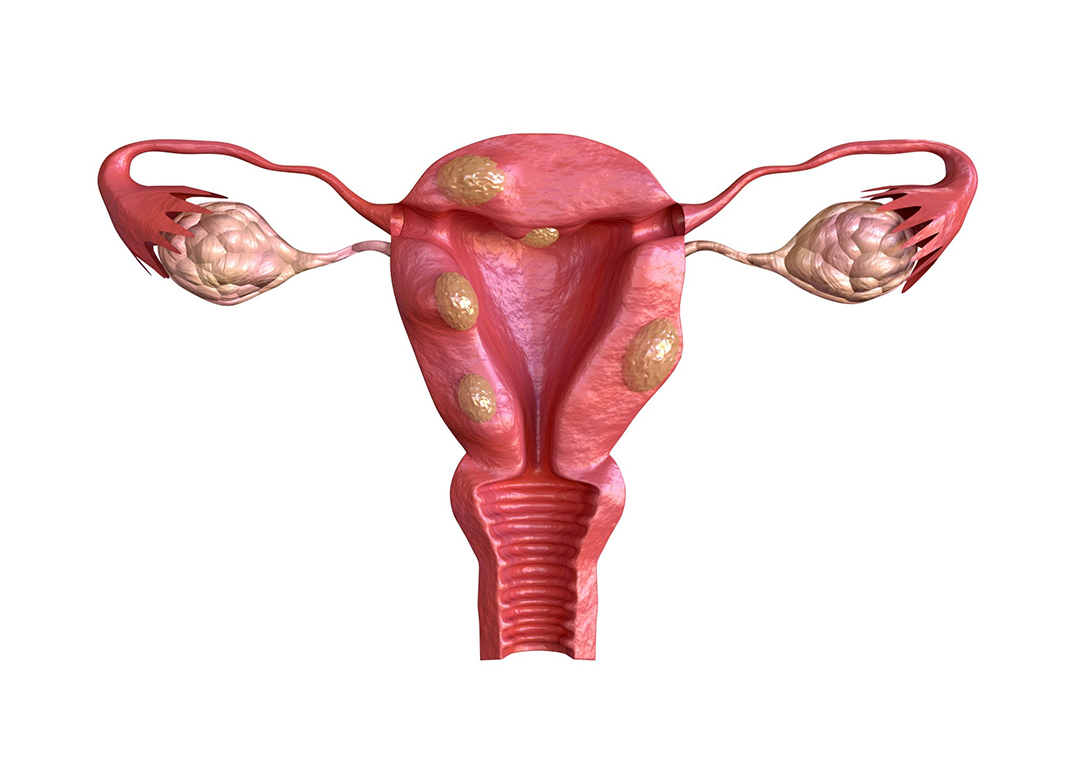

Subserous fibroids are a type of noncancerous growth that originates in the outermost layer of the uterus, medically known as the serosa. These fibroids are distinct from other uterine fibroids in terms of their location and growth pattern. Unlike their counterparts, which develop within the uterine wall or inside the uterine cavity, subserous fibroids project outward, often connecting to the uterus via a stalk-like structure.

To gain a deeper understanding of subserous fibroids, it’s essential to explore their anatomy. These fibroids typically start as small, benign tumors that form on the outer surface of the uterus. Over time, they may grow and extend away from the uterine wall. This unique growth pattern sets subserous fibroids apart and influences their impact on a person’s health.

Subserous fibroids can vary in size, shape, and number. Some may remain relatively small and inconspicuous, while others can grow significantly, leading to noticeable protrusions on the uterine surface. Understanding the different characteristics and variations of subserous fibroids is crucial for healthcare professionals to provide accurate diagnosis and tailored treatment plans.